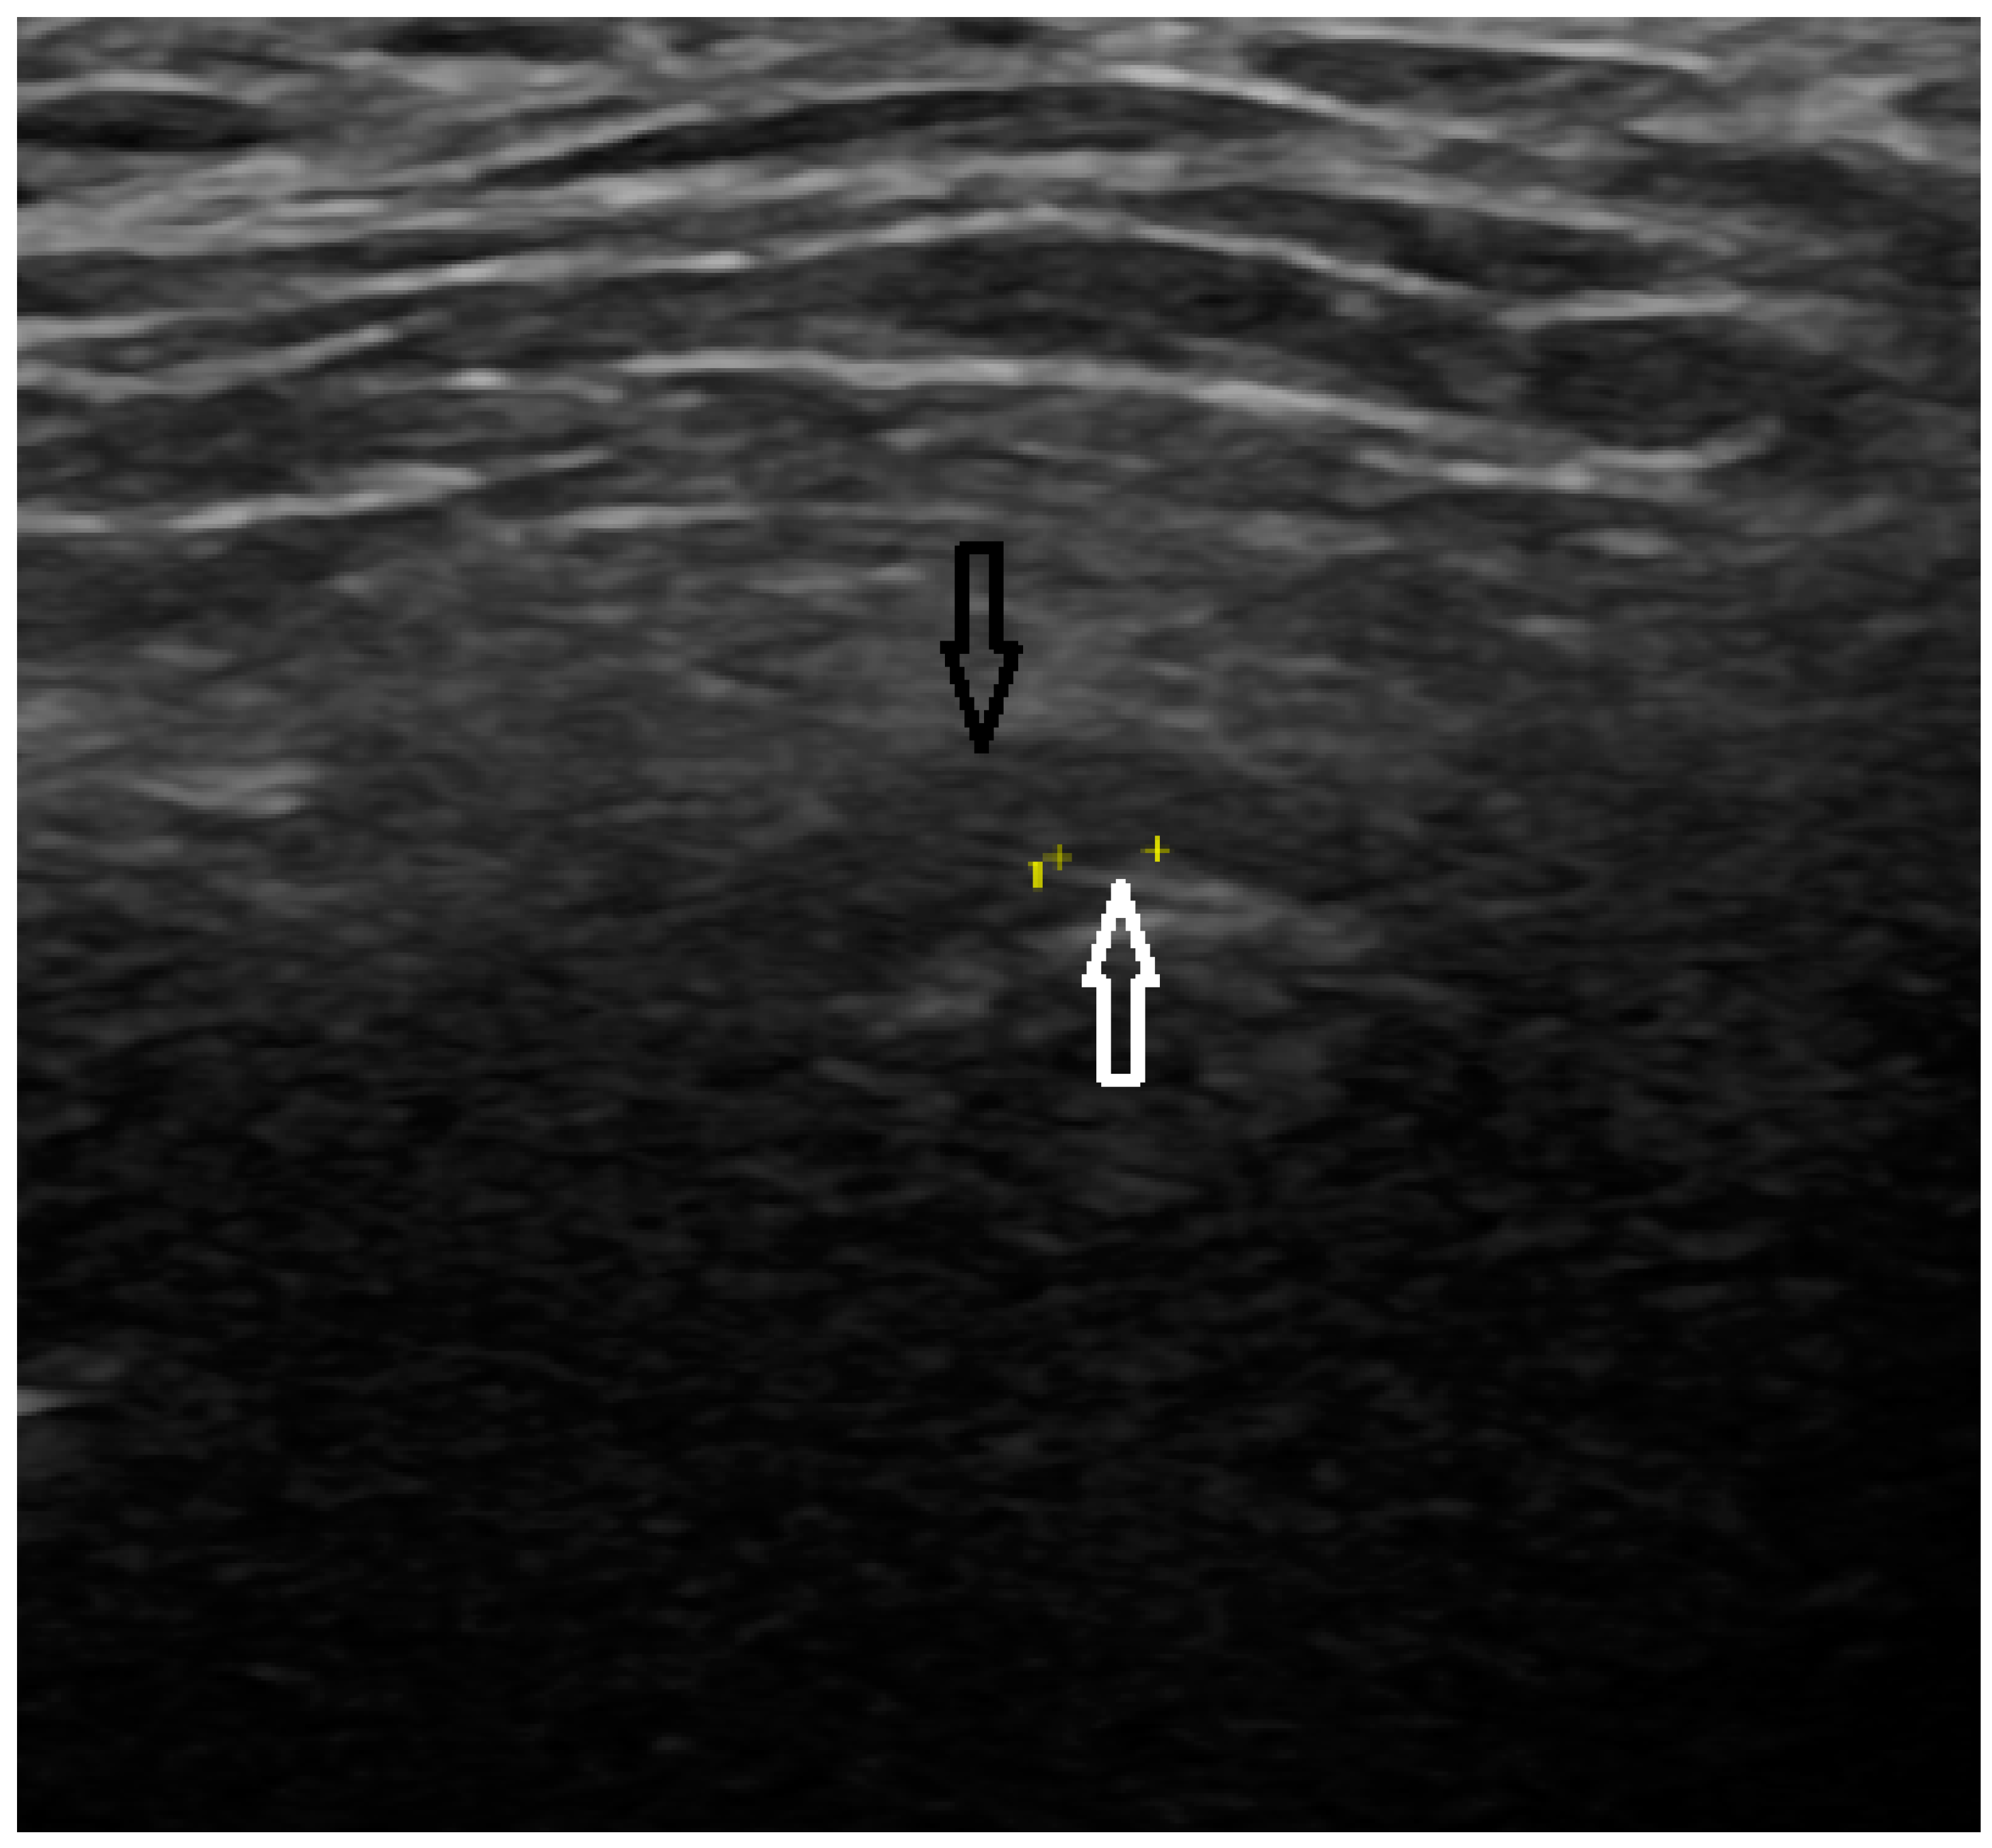

In the US analysis, we aimed to assess synovial effusion within the joint, which is indicative of inflammation or pathological fluid accumulation (Figure 2). Additionally, a thorough examination of the osseous structures was conducted. This included identifying the presence of osteophytes and evaluating any erosive changes to the bone surfaces. Furthermore, the analysis extended to the evaluation of the articular disc (Figure 3). For the purposes of the study, a unique research protocol was proposed, consisting of the assessment of the temporomandibular joint in the neutral position (mouth closed) with the mouth in maximum opening and the assessment of the path of the articular disc movement in a dynamic test. All examinations were performed by the same experienced radiologist using a LOGIQ E10 ultrasound with a dedicated L8-18i hockey stick linear probe (GE Healthcare, Boston, MA, USA).

Figure 3. Ultrasound (articular disc—black arrow, osteophyte—white arrow).